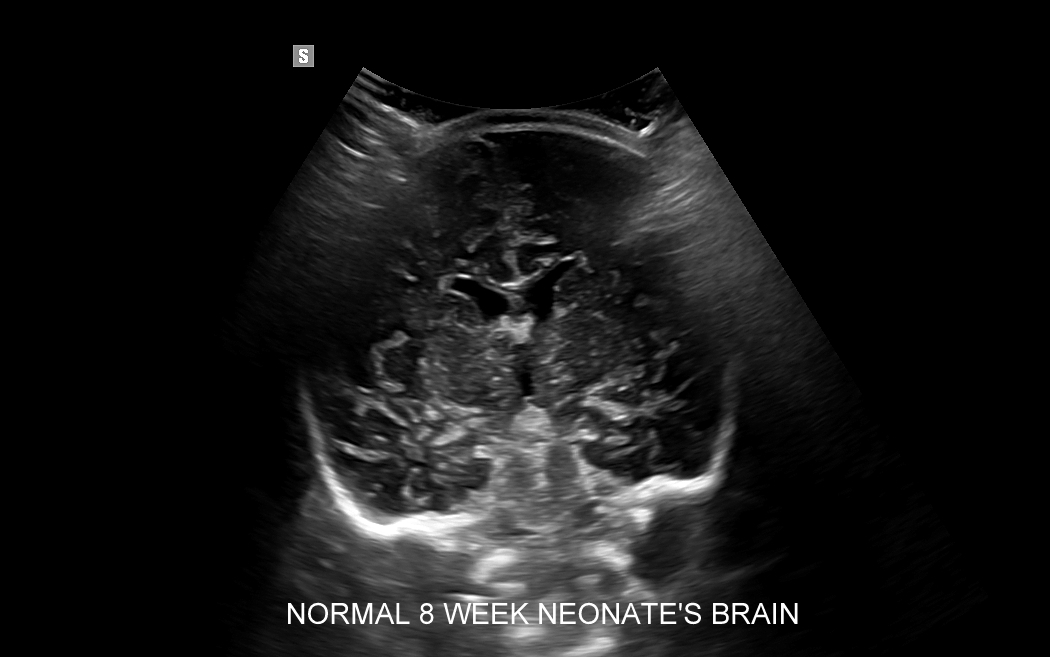

USG główki to podstawowa metoda diagnostyczna mózgu i struktur okołomózgowych u wcześniaków, noworodków i niemowląt. Badanie jest bezbolesne i nieryzykowne w porównaniu do rezonansu magnetycznego, podczas którego dziecko poddawane jest znieczuleniu ogólnemu. Przeprowadzenie szerokiego i szczegółowego badania USG główki jest możliwe aż do momentu zarośnięcia ciemiączka, czyli chrzęstnej struktury w pokrywie czaszki. Ze względu na cienką kość skroniową czaszki dziecka w późniejszym okresie możliwa jest wciąż częściowa ocena mózgowia w badaniu USG. Ambulatoryjne badanie USG przezciemiączkowe zwykle zalecane jest przez neonatologa, pediatrę lub neurologa dziecięcego w celu oceny mózgu wcześniaków, dzieci z małą masą urodzeniową, dzieci po epizodzie niedotlenienia lub krwawienia wewnątrzczaszkowego w trakcie porodu lub okresu noworodkowego, a także w przypadku wystąpienia drgawek, podejrzenia wady układu nerwowego, np. wodogłowia.

W USG główki dziecka oceniane są struktury wewnątrzczaszkowe, tj. mózg wraz z jego układem komór wewnętrznych, sploty naczyniówkowe, istota biała mózgu i obszary jąder podstawy mózgu, morfologia zakrętów i bruzd mózgowia, przestrzeń przymózgowa, a w trybach dopplerowskich wybrane naczynia tętnicze i żylne mózgu, w tym zatoki żylne. Oceniane są również cechy ciśnienia śródczaszkowego. W opisie badania podawane są również wymagane przez neurologa tzw. wskaźniki komorowe oraz wymiary wybranych struktur.

Badanie USG służy również ocenie dojrzałości mózgowia dziecka; otóż mózg wcześniaka różni się od mózgu starszego niemowlęcia. U tego pierwszego obserwuje się m. in. mniej zaawansowane bruzdowanie kory mózgowej oraz warianty rozwojowe, z których najczęstszym jest jama przegrody przezroczystej. Zaburzenia rozwoju kory mózgowej u płodu, a potem u niemowlęcia, obserwowane są w przypadku palenia papierosów przez ciężarną lub spożywania przez nią alkoholu, w przypadku powikłań przebiegu ciąży, a także powikłań okołoporodowych.